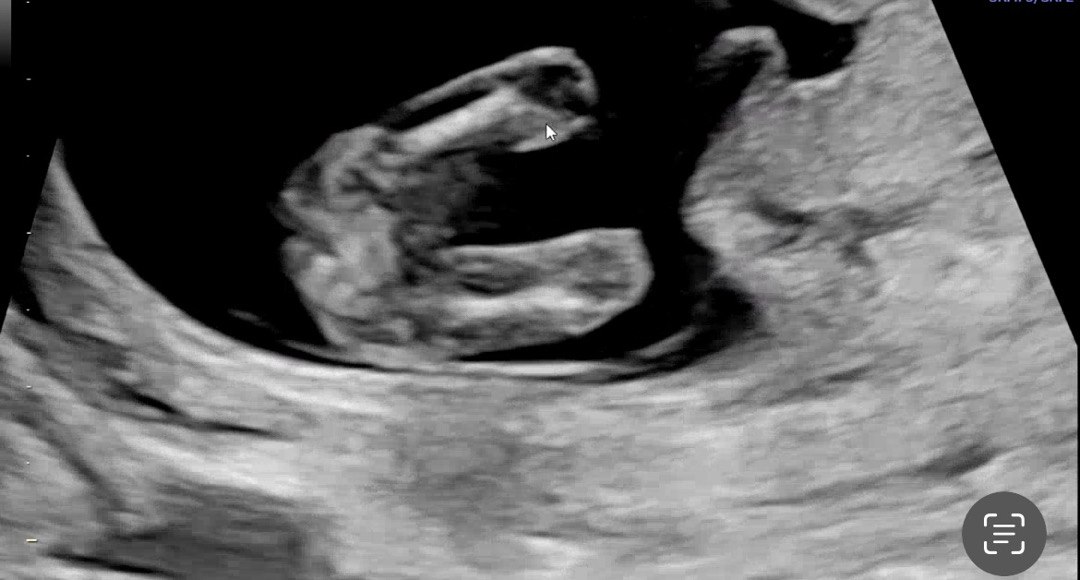

12주차 다리 사이에 이정도면

걍 아들인가요??

저도 12주차 이정도였는데 딸이에요 ㅎㅎ

뭔가가 있어보이는것 같은데요?